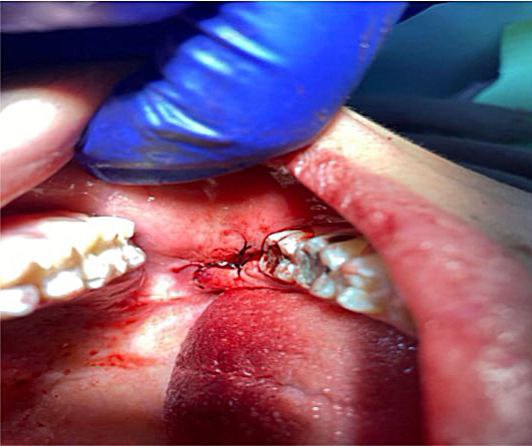

أجراء عملية قلع سن مطمور لمريض في عيادة جراحة الفم

أجراء عملية قلع سن مطمور بالفك السفلي لمريض زار عيادة جراحة الفم

عملية قلع جراحي لسن العقل في عيادة جراحة الأسنان

أجراء عمليات قلع جراحي في عيادة جراحة الأسنان